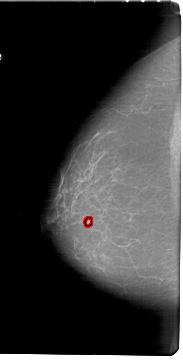

FILE: A_1800_1.LEFT_CC.OVERLAY

TOTAL_ABNORMALITIES 1

ABNORMALITY 1

LESION_TYPE MASS SHAPE LOBULATED MARGINS ILL_DEFINED

ASSESSMENT 4

SUBTLETY 3

PATHOLOGY BENIGN

TOTAL_OUTLINES 1

BOUNDARY